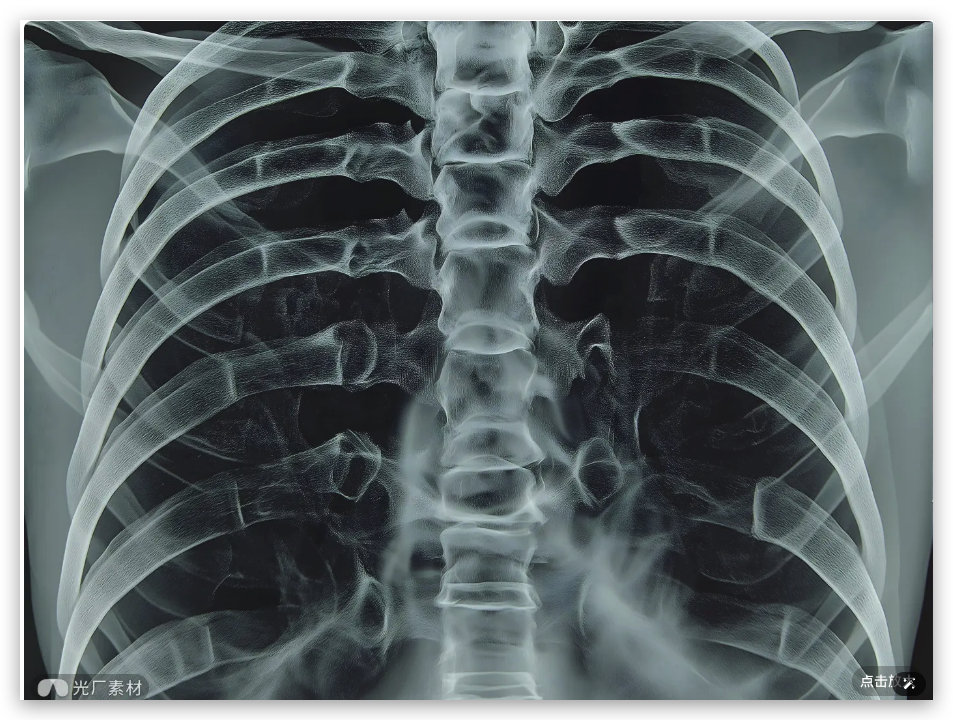

VLM 视觉模型另外一个使用场景就是在对医疗影像进行分析,比如:

提示词:这是一张胸部X光片,请检查一下肺部是否有异常结节。如果发现可疑区域,请圈出来,并大致测量一下它的最大径。另外,这张片子有点歪,请帮我把它旋转扶正,让脊柱保持垂直,看下效果。

Doubao-Seed-1.6-vision 就会依次自主调用工具,先是调用rotate进行旋转,

然后调用 zoom 工具进行局部多次放大:

从在复杂的《清明上河图》里找人,到分析X光片的细节,这些以前我们想都不敢想的场景,现在正一个个变成现实。